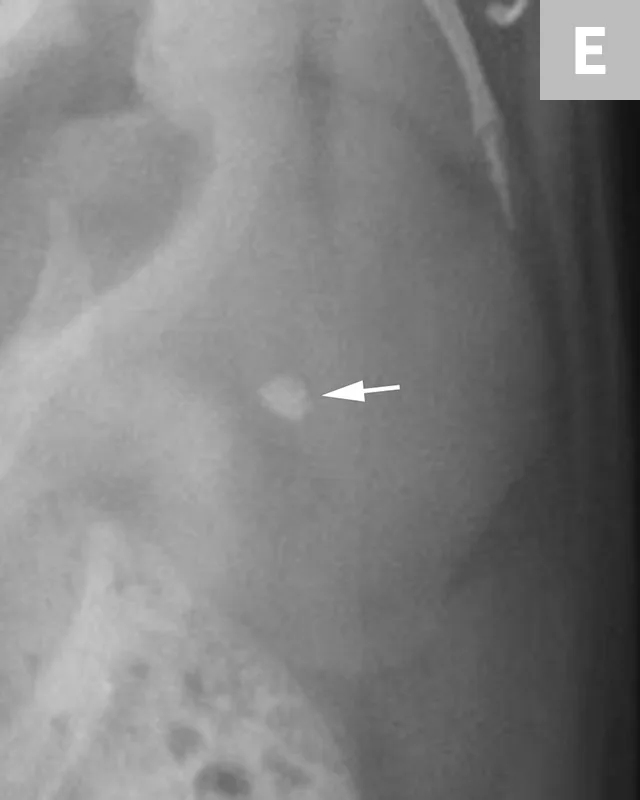

A separate center of ossification associated with the os penis may mimic a urethral calculus (Figure 11 A and B). A separate center of ossification can be seen at either end of the os penis and will be in line with the os penis. A calculus within the penile urethra would be seen ventral to the os penis in the location of the urethra. Contrast urethrography can be a helpful way to differentiate between a separate center of ossification and urethral calculus (Figure 11C).

FIGURE 11A

Lateral radiograph of a male dog collimated to include the urinary bladder and os penis. Note the well-defined mineral opacity just proximal to and at the same level as the base of the os penis—a separate center of ossification (arrow). Also note the two soft tissue opaque nodules summating with the prepuce, presumed to be small nipples (arrowheads).